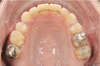

La contention peut être fixée, collée, il s'agit d'un fil de contention placé derrière les incisives: il ne dérange pas, il n'est pas du tout visible.

- Arc collé (fixe)